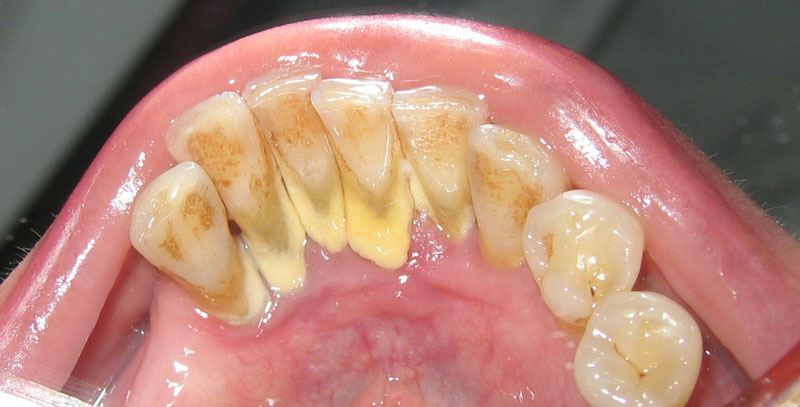

Hình ảnh cao răng mảng bám xung quanh răng

Quan sát bằng mắt thường: Cao răng có màu vàng hoặc nâu đen bám chặt ở vùng nướu và dưới vùng nướu, lâu ngày sẽ gây ra hiện tượng viêm lợi và chảy máu chân răng,.. Những trường hợp này cần phải đến ngay nha khoa để bác sĩ lấy cao răng và loại bỏ các vi khuẩn ẩn náu dưới đường nướu.